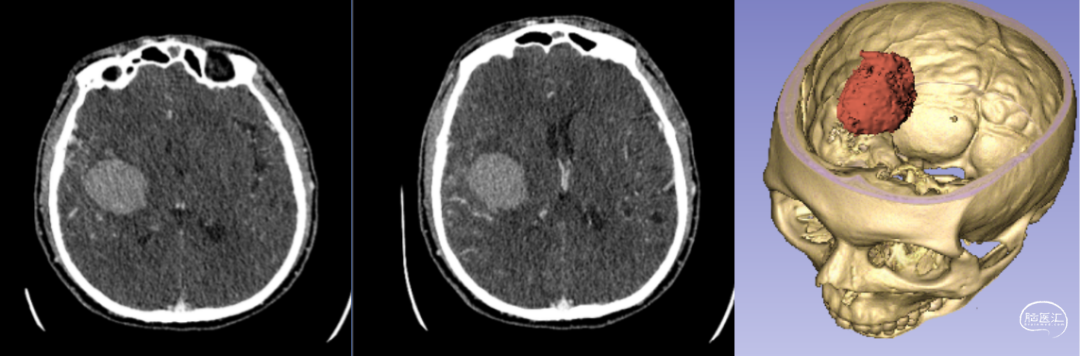

新疆醫(yī)科大學第一附屬醫(yī)院神經(jīng)外科中心已成功將該技術(shù)應(yīng)用于多例腦卒中患者的治療。以一例典型病例為例:[14]

- 患者情況:52歲女性,因“右側(cè)肢體無力1天”就診,入院時呈淺昏迷狀態(tài),雙側(cè)瞳孔等大等圓(直徑約3.5mm),對光反射遲鈍,右側(cè)肢體肌力為0級。

- 手術(shù)過程:基于術(shù)前影像數(shù)據(jù),團隊利用3D打印技術(shù)設(shè)計并制作個性化手術(shù)導板,精準定位血腫位置后實施穿刺引流。術(shù)后復(fù)查頭部CT顯示,引流管準確位于血腫腔內(nèi),血腫清除效果良好。